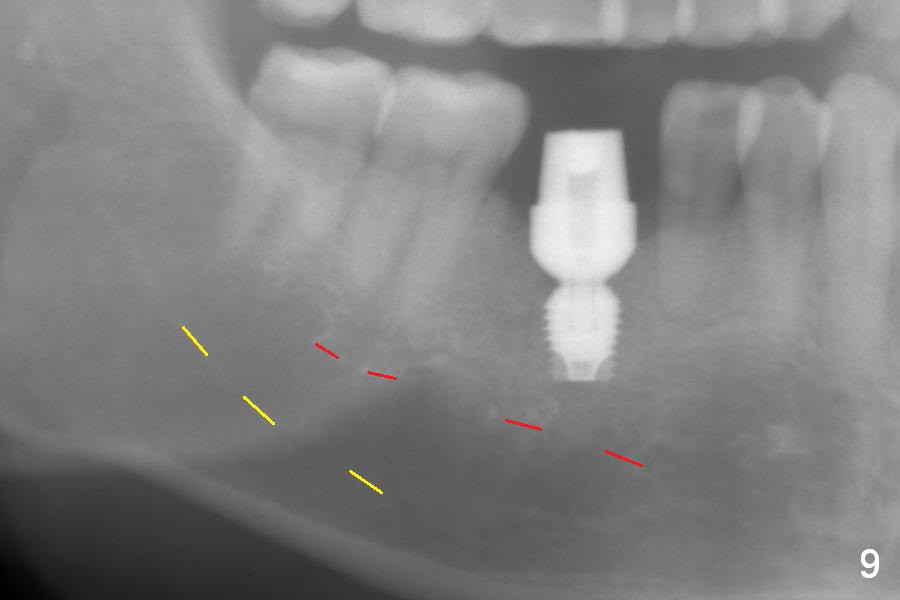

After extraction of the tooth #30 with Class V furcation involvement (Fig.1 (>),2 (L: lingual)), initial osteotomy depth is 8 mm with infiltration anesthesia, but a parallel pin is able to be inserted for 16 mm without pain (Fig.3). There is oozing from the osteotomy. Osteotomy increases in diameter with depth at 8 mm (Fig.4 (3.8 mm drill),5 (5.3 mm tap)). As the Inferior Alveolar Canal (IAC) is indistinct with increased pain during osteotomy, a 5.9x6 mm implant is placed with >50 Ncm following Septocaine infiltration (Fig.6). When bone graft (Fig.7 *) and 7.8x5.5(6) mm abutment (Fig.7,8) are placed, panoramic X-ray is taken (Fig.9). There appears to be a thick layer of spongy bone in the posterior mandible between the red and yellow dashed lines (Fig.5,9). Panoramic X-ray and/or CBCT should be taken if preop PA does not reveal IAC. This patient seems to be a bruxer. There are mandibular tori. Bone loss (furcation involvement) is not proportional to his oral hygiene status. Functional loading (progressive) should be delayed due to bruxism and the short implant.